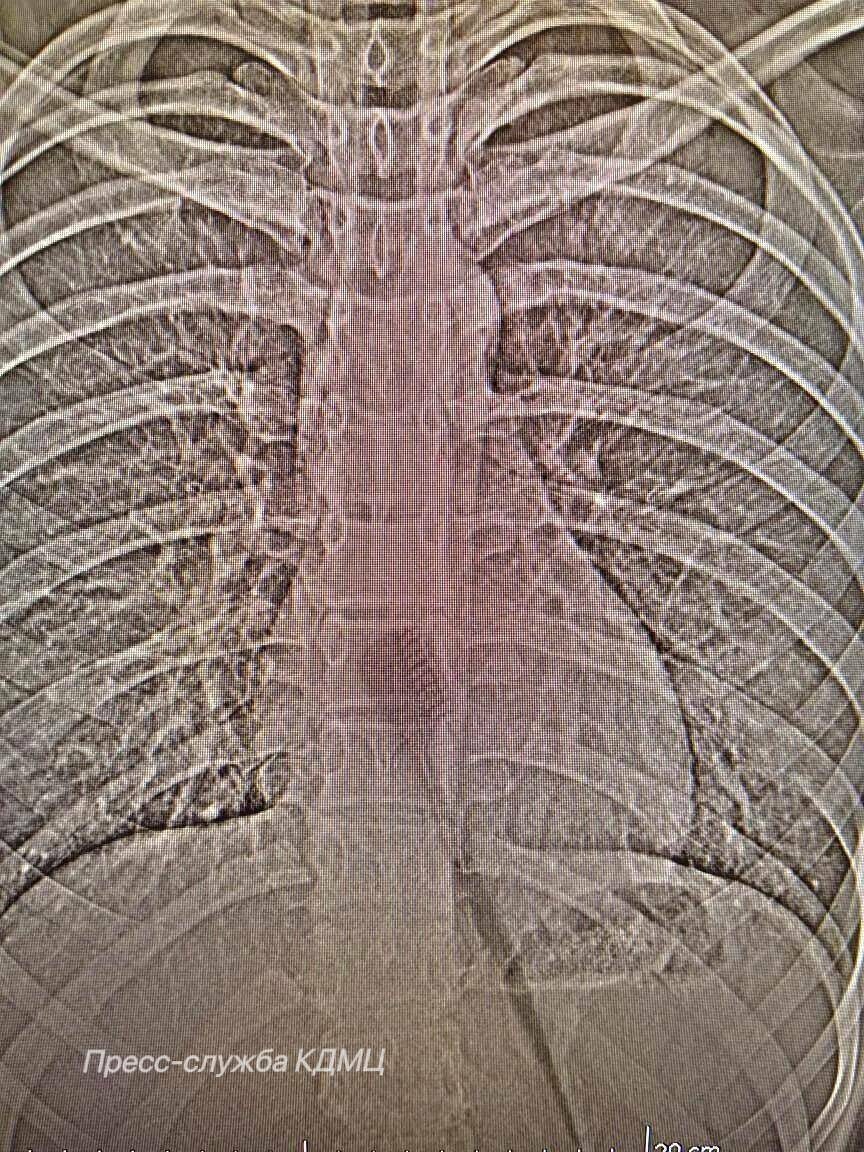

Фото: пресс-служба КДМЦ

В детскую больницу поступила 13-летняя пациентка, случайно проглотившая зубную щетку длиной 19 сантиметров во время утренней гигиены. Щетка находилась в желудке и частично в пищеводе, создавая риск повреждения этих органов.

Девочке провели эндоскопическую операцию – это позволило врачам аккуратно удалить предмет через естественные пути, минимизируя риск осложнений и ускоряя процесс восстановления пациентки.